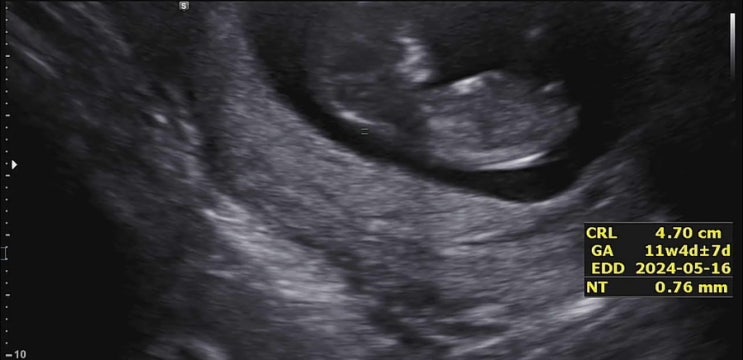

임신 11주 12주 15주 16주 1차 기형아검사 2차 기형아검사 목투명대검사

저는 임신기간 중 가장 긴장되었던 순간을 꼽으라면 첫번째로 기형아검사라고 할 것같아요 검사를 앞두고 ...